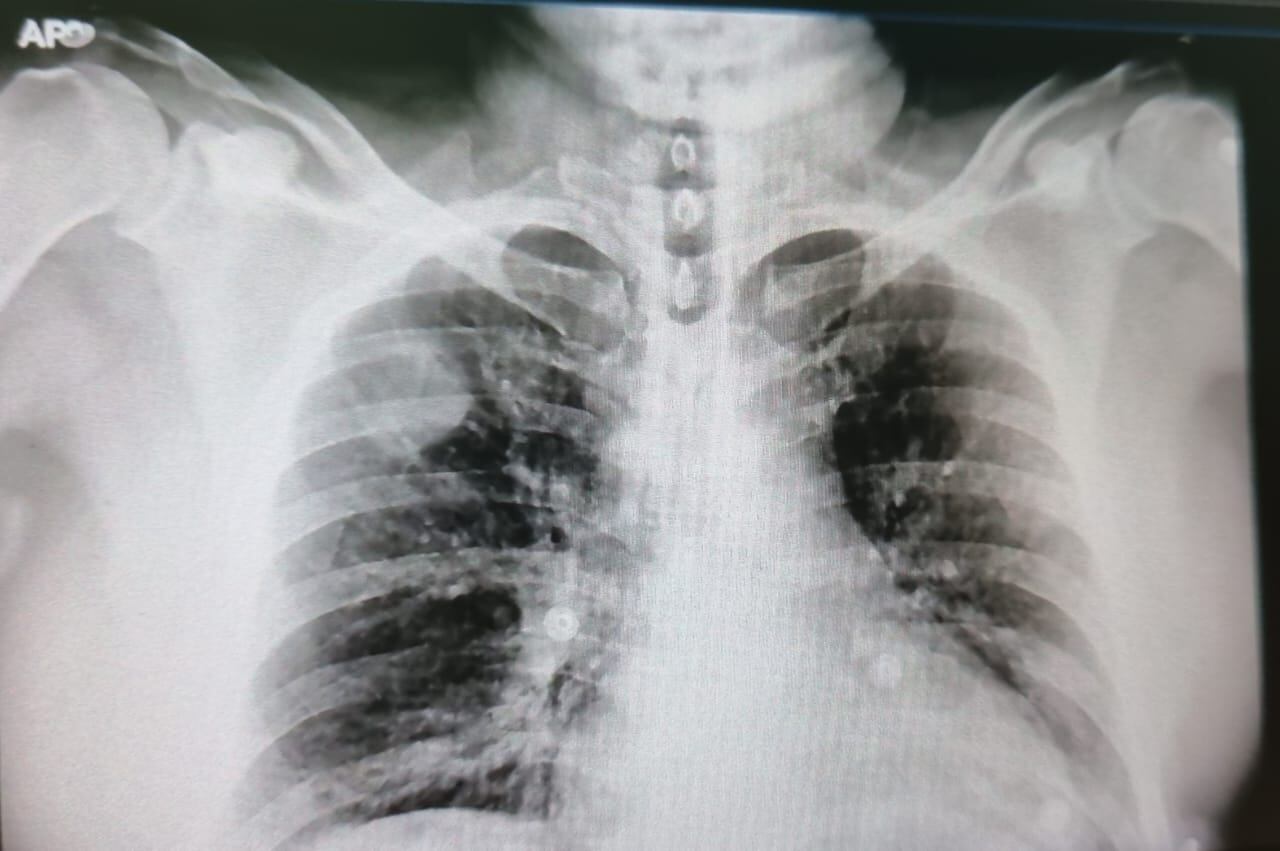

“Yo venía complicado, traía neumonía muy avanzada en los dos pulmones. Supongo que la tos me afectó mucho. Me pusieron un oxígeno leve cuando llegué, pero luego determinaron que el problema mío era serio y me pasaron a cuidados críticos”, explicó.